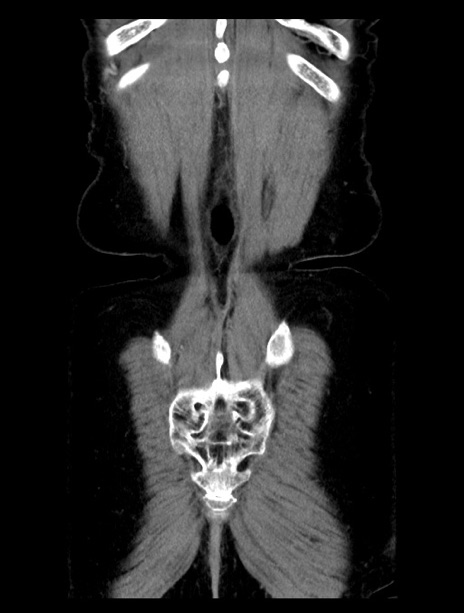

症例23(冠状断像)

【症例】70歳代女性

【主訴】下腹部痛・嘔吐

【現病歴】2日前より腹痛あり。昨日嘔吐あり。症状改善しないため来院。

【既往歴】胃GISTに対して胃部分切除後。

【身体所見】BT 37.1℃、BP 128/77mmHg、腹部:平坦・軟、下腹部に圧痛あり。

【データ】WBC 10200、CRP 0.31